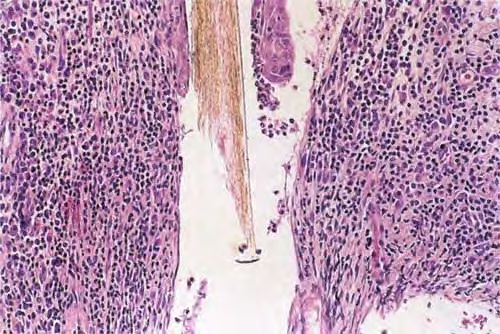

Dissecting cellulitis of the scalp =التهاب النسيج الخلوي المسلخ على فروة الرأس